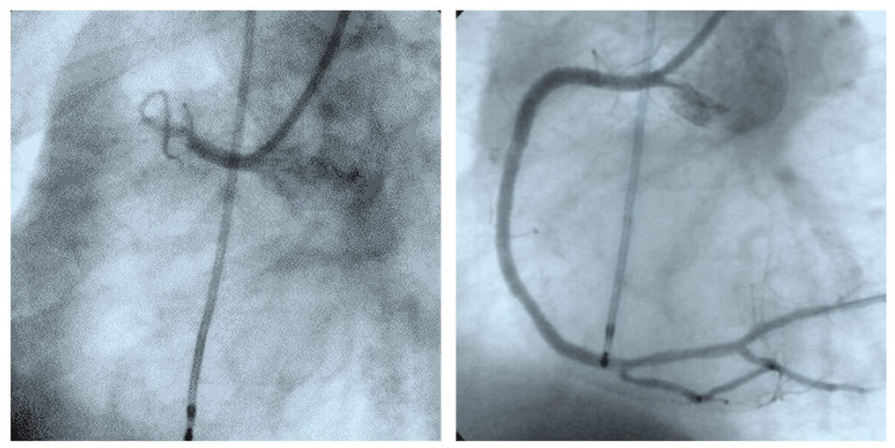

심근경색이 의심되는 경우, 즉각적인 응급처치가 필수입니다. 급성심근경색증상이 나타나면 119에 전화하여 도움을 요청하고, 환자를 편안한 자세로 눕히며, 산소를 공급해야 합니다. 병원에 도착하면, 의사는 ECG(심전도)와 혈액 검사를 통해 진단을 진행하며, 심장 카테터 삽입술이나 스텐트 삽입 등 다양한 의료적 처치를 진행합니다. 이러한 치료는 신속하게 이루어져야 심장 근육의 손상을 최소화할 수 있습니다.